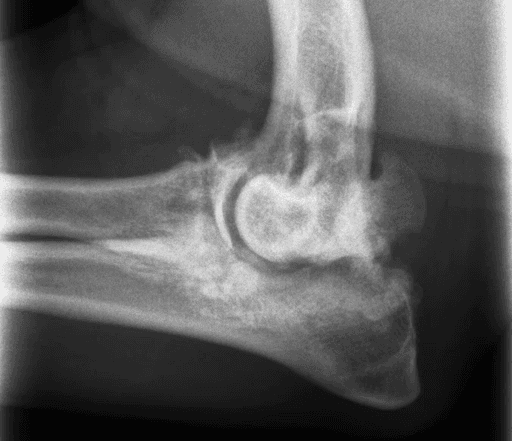

UAP

Ununited Anconeal Process (UAP): Failure of a growth plate within the ulna to close normally, leading to separation (fracture) of the anconeal process.